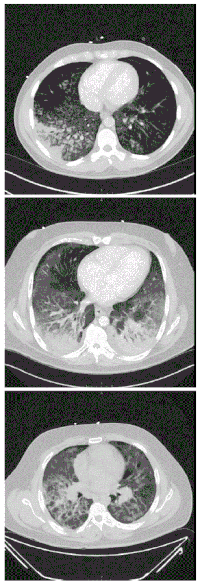

| CT scan of the chest showing diffuse lung infiltrates found in three cases of vaping-associated pulmonary injury | |

There are non-specific laboratory abnormalities that have been reported in association with the disease, including elevations in white blood cell count (with neutrophilic predominance and absence of eosinophilia), transaminases, procalcitonin, and inflammatory markers.[4][59] Infectious disease testing, including blood and sputum cultures and tests for influenza, Mycoplasma, and Legionella were all found to be negative in the majority of reported cases.[59] Imaging abnormalities are typically bilateral and are usually described as "pulmonary infiltrates or opacities" on chest X-ray and "ground-glass opacities" on chest CT.[4]